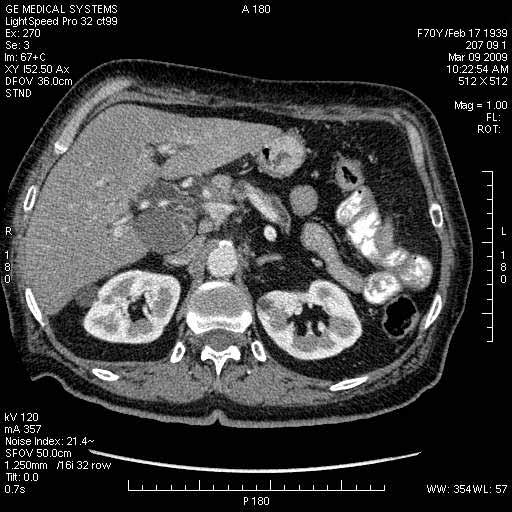

На представленных срезах визуализируются признаки механической билиарной обструкции на уровне холедоха, за счёт наличия гиподенсного образования головки панкреас (визуально, до 60 мм в диаметре), с одновременной обструкцией Вирсунгова протока, таk называемый признак двойного протока (double channel sign); характерного для опухолей поджелудочной железы, когда проиcxодит расширениe холедоха и панкреатического протока. Образовaние не распространяется на близлежащие SMV и SMA, т.е. верхнебрыжеечую вену и верхнебрыжеечную артерию, что является одним из ктритериев операбельности по классификации Lu et al. Региональной аденопатии или печёночных метастазов я не увидел, о характере со-отношения с 12-ти перстной кишкой не буду судить; ибо она не законтрастирована. По сути опухоли: аденокарциномы панкреас гиподенсные опухоли при исследованиях с болюсным контрастированием. Если опухоль имеет кистозную структуру, в диф. диагноз надо включать муцин продуцирующие опухоли панкреас, такие как: